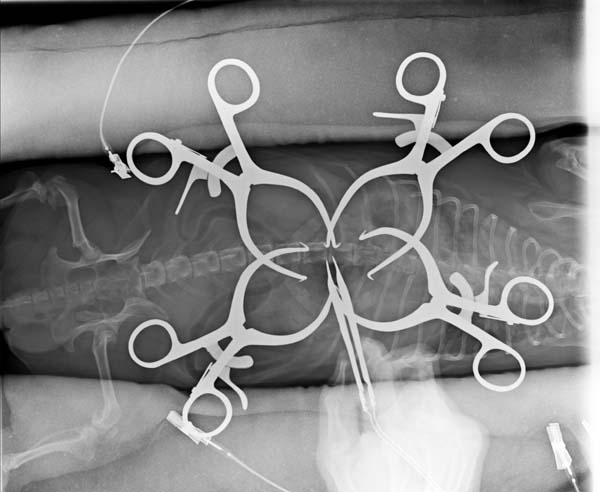

5~6歳以上の去勢手術をしていないオス犬に多い病気ですが、メス犬や去勢した犬に起こることもあります。お尻の筋肉が萎縮した結果、筋肉の隙間から直腸や膀胱が皮膚の下にとびでてしまいます。これにより便が出にくくなったり膀胱炎になったりします。手術をすることで機能回復および今後の致死的な状況を回避することができます。当院では去勢手術→結腸固定→前立腺固定→骨盤隔膜構成筋の縫縮→内閉鎖筋フラップ→浅臀筋フラップの順で通常腹側・臀部左右両側同時に行います。また老化以外に、筋肉が萎縮する原因があったり、腹圧がかかる原因があったりする場合も多いので、再発防止のためそれらの診断・治療も重要です。今回のワンちゃんも無事手術も終わり元気に退院しました。よかったね。